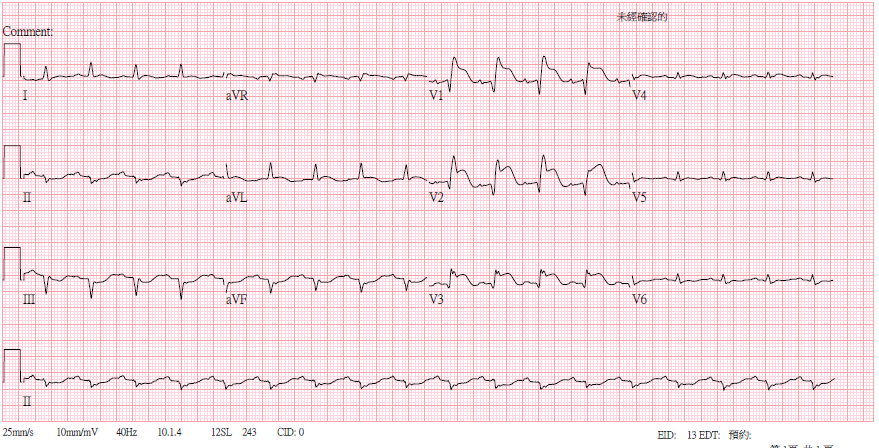

A 24-year-old womanexperienced nausea and abdominal discomfort days before a shortsyncope episode. She was taken to a local hospital. EKG showed sinustachycardia, low QRS voltage, and ST elevation over aVR, V1-3. CT scan of the brain revealed no signs of intracranial hemorrhage. Shewas transferred to our hospital under norepinephrine infusion.

We report a youngwoman with fulminant myocarditis, who survived with temporary Impella CP® support. An initial ECG showed ST elevation in V1 and aVR, indicatingpossible right ventricular involvement. For circulatory support, wechosed Impella CP® because VA-ECMO would increase afterload, leadingto pulmonary edema and poor LV recovery. Even RV was involved withimpaired RV function, her clinical condition remained stable underthe treatment guided by PAC. By day 3, her cardiac function hadimproved much, and the Impella CP® was removed on day 5. The patient wasdischarged on day 11. One-month follow-up showed full RV and LVrecovery.